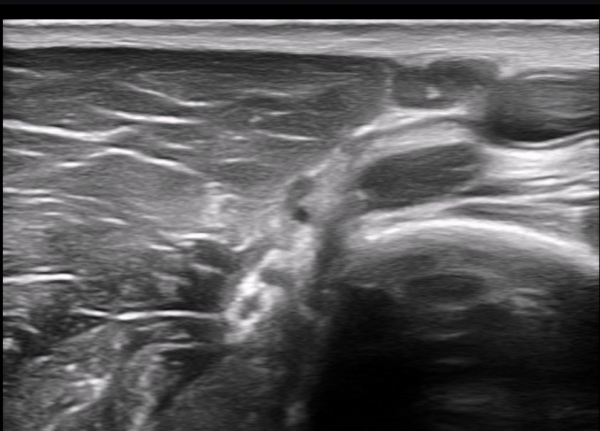

±ÙÀ°ÇǺνŰæÀÇ Á¾´Ü¸é°Ë»ç¿¡¼­ ±ÙÀ°ÇǺνŰæÀÇ ±¹¼ÒÀû ÇùÂø°ú ±ÙÀ§ºÎÀÇ Àú¿¡ÄÚ ºÎÁ¾ÀÌ °üÂûµÈ´Ù

(»çÁø 4, 5, 6,7) À̰ÍÀº ½Å°æÀÇ ¿°Àü(torsion)¿¡ ºÎÇÕÇÏ´Â ¼Ò°ßÀÌ´Ù.

½Å°æ º´º¯ÀÇ ÇǺο¡ Ç¥½Ã ÷ºÎÆÄÀÏ 5